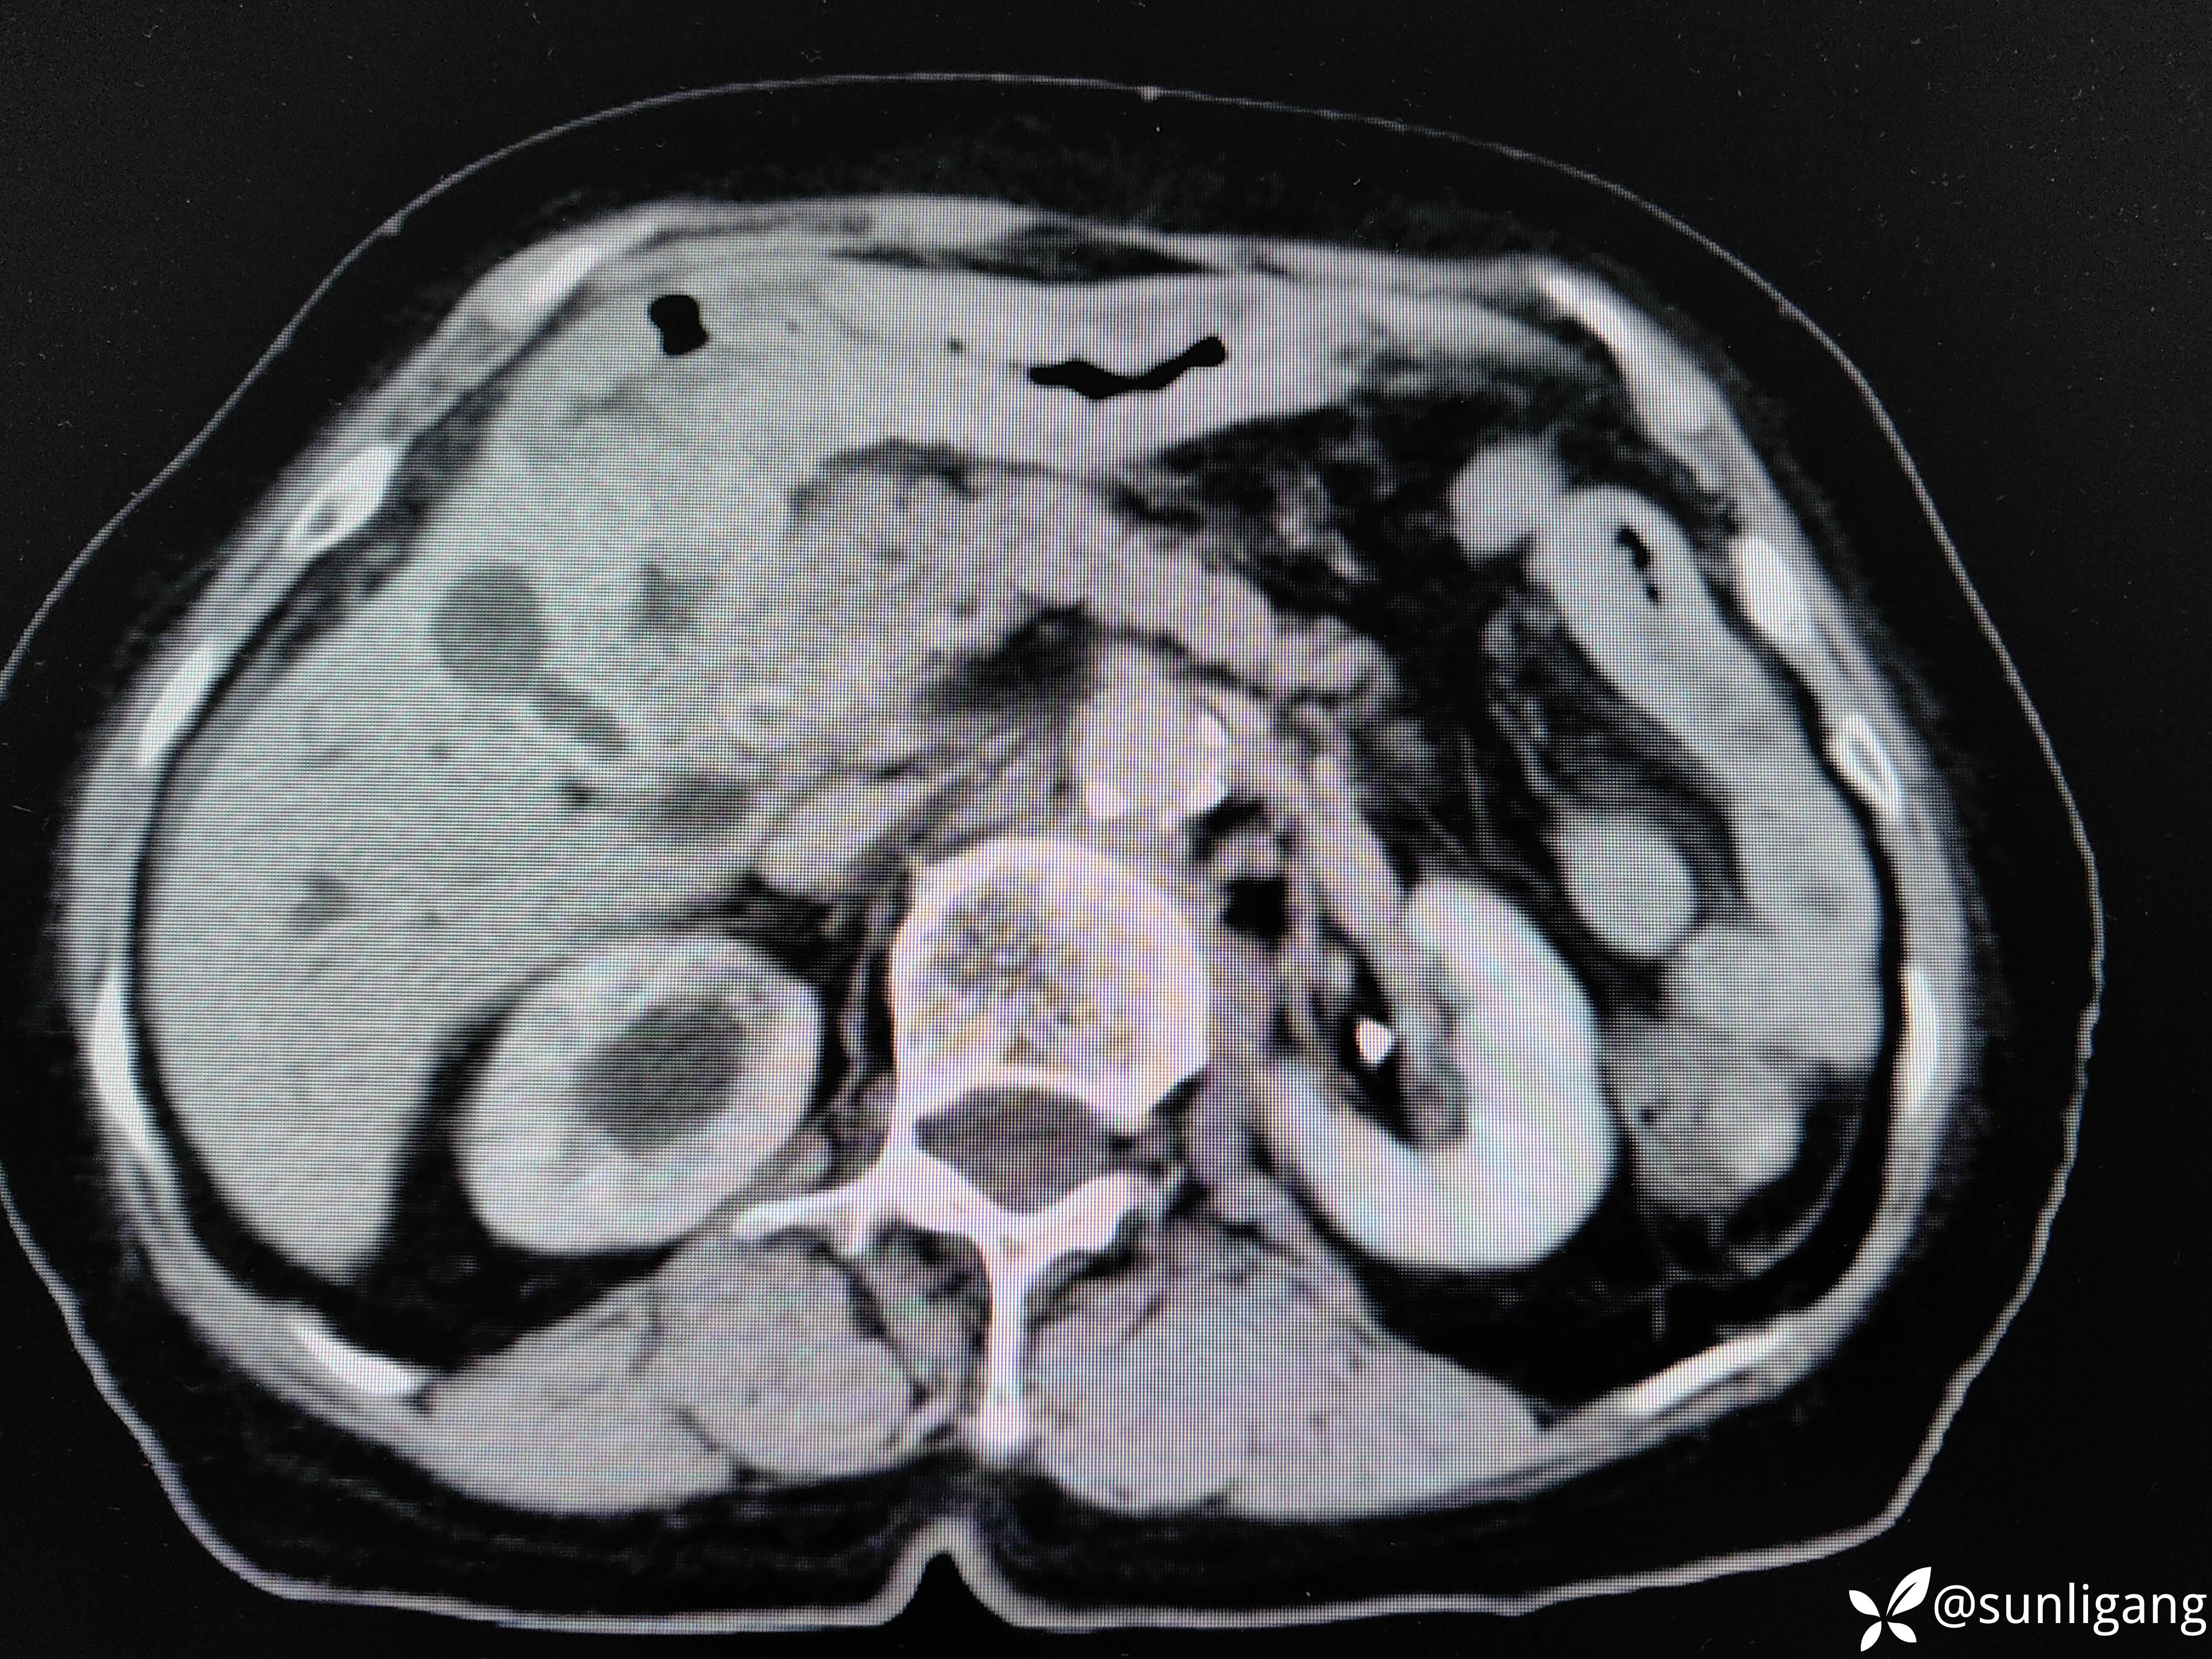

磁共振:

可见明显胆囊结石影

可见中断的中段胆管影以及扩张的肝总管、正常的胰管

可见明显变窄的胆总管(肿瘤直接侵犯?压迫?)